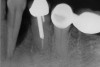

In treatment planning, the decay rate of the patient’s teeth, including the endodontic status of the individual tooth, becomes an important factor when considering long-term outcomes. In the pictured case (Figure 5), tooth No. 11, which previously had been treated endodontically, had recurrent decay and tooth No. 12 had advanced decay with endodontic involvement. In less than 30 days, recurrent decay that reaches the endodontic fill through a leaky restoration (temporary or not), ill-fitting crowns, or broken fillings can re-infect the entire length of the root canal system in a previously endodontically treated tooth.22 Therefore, saving a previously endodontically treated tooth, as in this case, may involve endodontic re-treatment, which can be a deciding factor for tooth preservation.

Figure 5  Recurrent decay of teeth Nos. 11 and 12. Note the proximity of the decay on both teeth to the osseous crest.

Figure 5